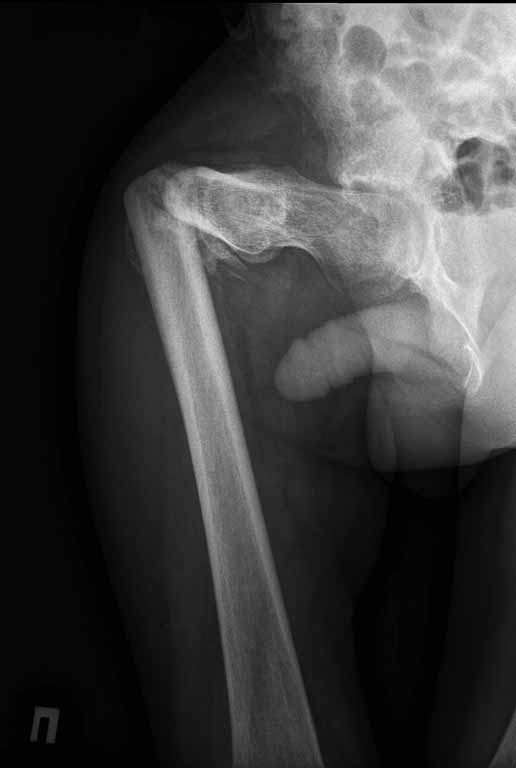

Пациенту 22 года. Травма в июле 2010г, лечился в районной больнице. К нам попал в апреле 2011г.Тяжелая сочетанная травма (29.07.2010): тупая травма живота с повреждением внутренних органов. Закрытая травма грудной клетки с переломом ребер. Пневмоторакс справа. Тяжёлая позвоночно-спинномозговая травма. Закрытый осложнённый переломо-вывих С5 позвонка. Верхний парапарез, нижняя параплегия, нарушение функции тазовых органов по типу недержания. Цекостома. Пролежень левой ягодичной области. Неправильно консолидированные переломы верхних третей обеих бедер. Застарелый вывих левого бедра.Осложнение: Поддиафрагамльный абсесс слева, забрюшинного пространства. Свищ желудка и ободочной кишки. Синегнойный сепсис. Двухстороняя пневмония. Но это уже анамнез.Пациент был неоднократно оперирован на органах брюшной полости и осложнениями с ними связанными.

В ягодичной области слева глубокий пролежень размером 2х2см, дном является вывихнутая головка бедра. Неврологически в нижних конечностях динамика положительная, появились движения в правой стопе, чувствительность в стопах.По переломам бедер: подвижности в местах переломов нет, снимки высылаю.

Уважаемые коллеги, помогите определиться с оптимальной тактикой в лечении перелома бедер. Степень оснащенности у нас достаточная (аппараты, штифты, пластины, ЭОП).

Планирую начать с правого бедра, ЧКО таза (передняя рама) с фиксацией бедра. О/клазия места перелома правого бедра и устранение грубых смещений в аппарате. окончательно можно оставить и в аппарате. Далее аппаратное устранение вывиха левого бедра.